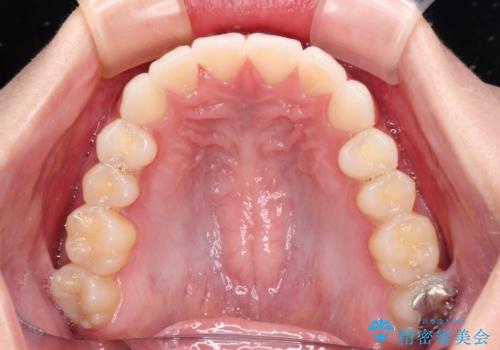

- 前歯2本が飛び出してることを気にして来院された患者様です。

全体的に黄ばんだ歯の色も気になるとのことで、マウスピース矯正により飛び出した前歯を治しつつ、ホームホワイトニングを併用して黄ばみを解消していくこととしました。

歯と歯の間を削ることで、飛び出した前歯が引っ込み、スッキリとした口元となりました。

歯の黄ばみも改善され、明るい歯並びとなりました。